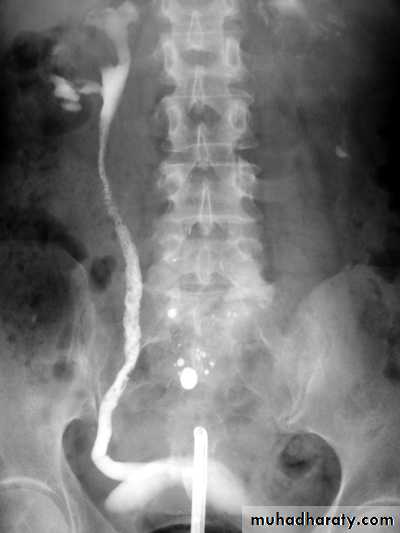

Antegrade&Retrograde pyelographyTheir indications are limited to situations where the information cannot be achieved by less invasive means like IVU or CT to confirm a possible TCC in renal pelvis or ureter.

Almost all tumors that arise in the PCS are TCC.Sometimes occur at multiple sites (so both PCSs and ureters should be examined).

IVU plays important role in their Dx.

Ddx of TCC on IVU are stones and blood clots.